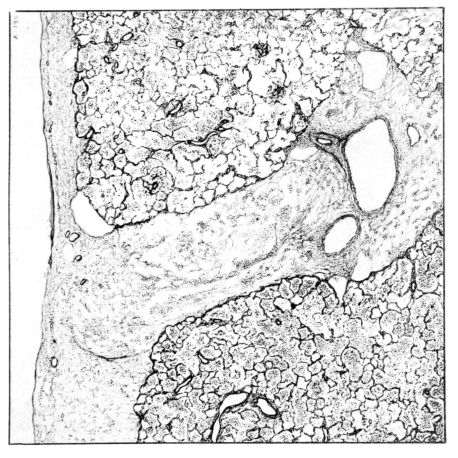

FIG. II. AUTOPSY NO. 98. DRAWING OF A SECTION THROUGH A TRACHEA SHOWING NECROTIZING HEMORRHAGIC INFLAMMATORY PROCESS OF THE MUCOSA.

The changes are less marked, perhaps, in the trachea than in its finer ramifications. The mucosa is constantly more or less destroyed and large areas, usually focal, are entirely devoid of their epithelial covering. This is replaced by a sparse exudate, composed largely of red blood cells, mucus, a small amount of fibrin, and nuclear fragments (Fig. II). It may dip into the submucosa for a short distance, but usually these indentures are associated with the ducts of the mucous glands into which the inflammatory reaction extends. A more striking feature than the exudate, however, is the edema and the congestion of the submucosa. The loose areolar tissue of the submucosa is spread widely apart, and throughout it distended blood vessels are very conspicuous. Occasionally such a vessel is broken and actual hemorrhage appears in the submucosa. Occasionally, too, the inflammation extends down the duct to the mucous gland itself, and here, also, aplastic inflammatory reaction is evident, inasmuch as the acini now stain intensely red with the cells undifferentiated from each other and specked here and there by broken remains of the dead nuclei (Fig. III). After the disease has continued for a short period, even at the end of five or six days, some regeneration of the epithelial lining may be seen (3) (Fig. IV). But despite this, the acute picture persists, and there goes on, side by side, an attempted repair characterized by epithelial regeneration and the same evidence of acute change. Since the lesion is essentially a superficial one, scars or contractures of any extent are not encountered in the trachea, even in examples of the disease that have ended fatally only after many weeks.[4]